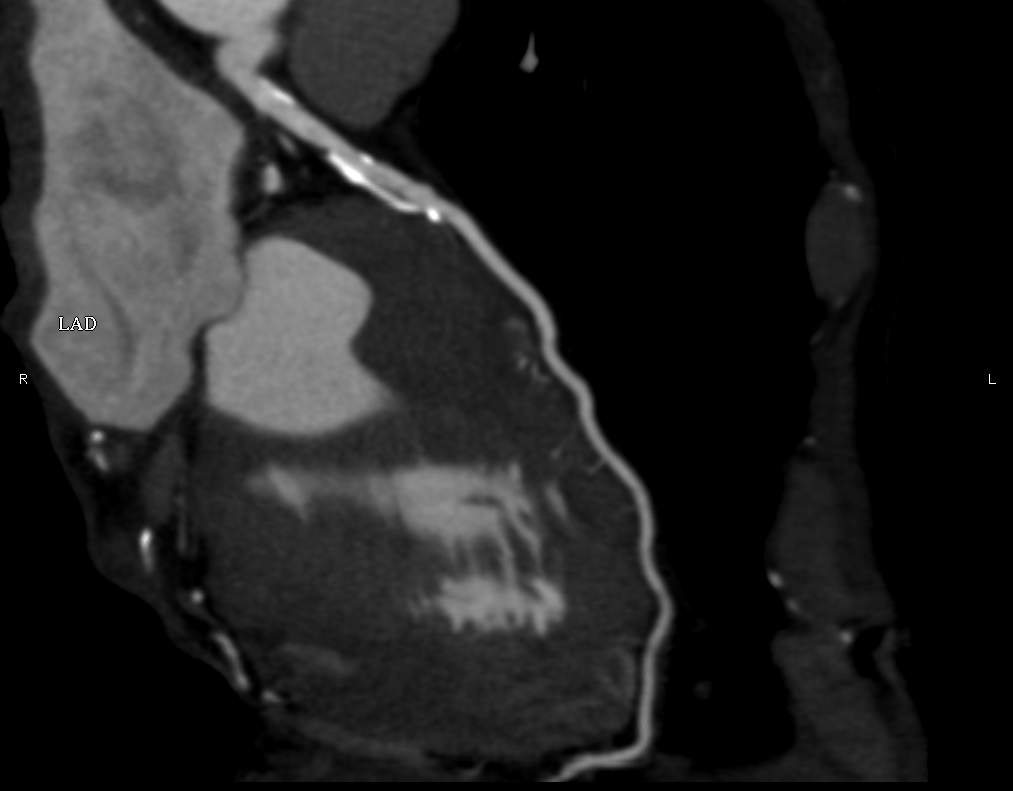

Fig. 3., 4., 5.: CT coronarography: Normal anatomy, volume rendered image and curved reformatted image Plaque causing stenosis on LAD coronary artery

The conventional imaging modality of the coronary vessels is cardiac catheterization (coronarography) which is still an absolute indication in acute coronary syndrome. During the examination besides identification of the symptom causing stenosis or occlusion (culprit lesion), it is also possible to perform dilatation with a balloon catheter or stent implantation to restore flow. If either of these procedures is carried out within 6 hours of symptom onset, myocardial tissue dearth can be prevented or minimalized. Coronarography of patients with stable angina is only recommended if a high risk of coronary disease persists clinically. CT coronarography can replace cardiac catheterization in low and medium risk patient groups who present with angina-like chest pain. The examination has a very high sensitivity and negative predictive value for coronary disease; therefore, it is a sensitive screening tool for patients who present with chest pain as a symptom of coronary stenosis. It can also uncover alternative diagnoses for chest pain syndromes. CT examination is not only good in representing the vascular lumen, but it can also detect non-stenosing but vulnerable (lipid rich) plaques by showing a special morphologic appearance. These lesions might remain hidden during coronarography, producing false negative results with regard to an existing significant atherosclerotic involvement.